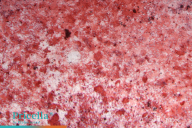

Figure 2. Identification of trilineage differentiation of MSCs from various sources